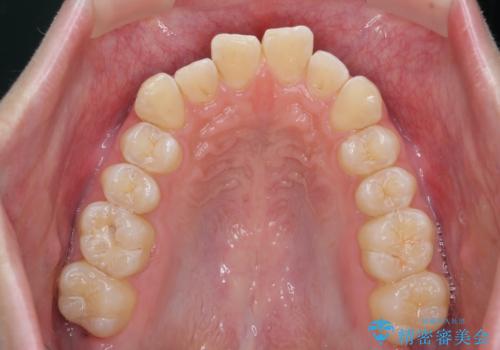

クロスバイト・歯並びが原因の歯肉退縮歯、矯正治療による審美性の改善

- 前歯の歯並び、下顎前歯の歯ぐきの下がり(歯肉退縮)の改善を求めて来院されました。

歯肉退縮の根本的な原因はすれ違った噛み合わせによる為害性のある咬合状態にあるため、歯肉退縮に対し結合組織の移植術を行うのではなく当該歯を抜去し部分矯正を含めた治療計画を立案します。

矯正治療を行ったことで、噛み合わせが安定し審美性も機能性も向上することができました。